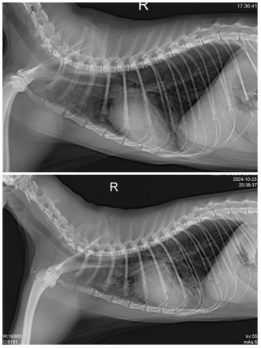

First, we conducted a chest X-ray, which revealed diffuse increased density in the lungs, potentially indicating fluid accumulation, and suggesting a possible heart issue. Additionally, the X-ray showed bronchial signs and an unclear heart silhouette, hinting that the heart might be enlarged or have other abnormalities.